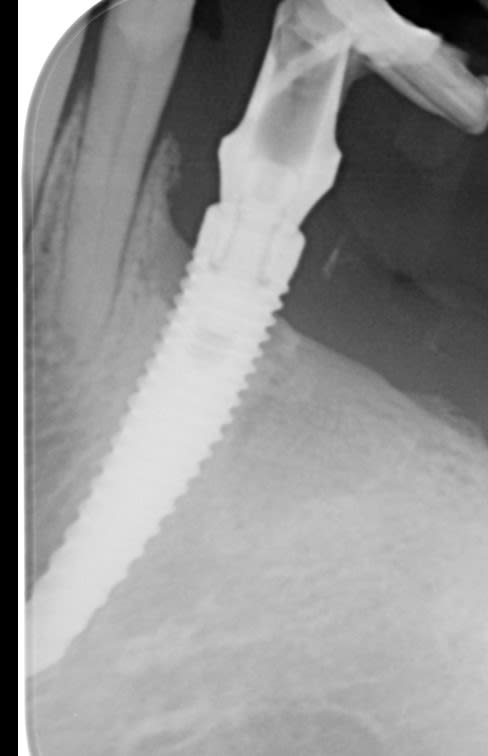

Et celui là.... je sais la radio est pas top mais implant long, bouche etroite.... j'ai pas pu faire mieux (et pourtant j'ai essayé)

Poseur injoignable ou pas coopératif.... machin posé en 2012 2013 à coté de 3 MK3 branemark de 10mm

20/09/2022 à 16h09

une pano par hasard en complément?

parce que là c'est très déformé....

Photo de la pano